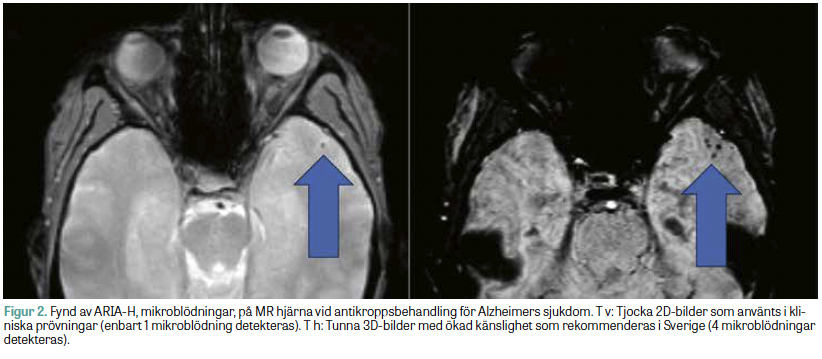

För att detektera och följa ARIA bör helst en MR-kamera med en fältstyrka på 3 Tesla användas, eftersom känsligheten för blodnedbrytningsprodukter ökar med fältstyrkan. Det är dock inte bara fältstyrkan som spelar roll. I de kliniska prövningarna har ofta enkla MR-sekvenser använts med tjocka (5 mm) 2D-snitt, bland annat traditionella T2*-viktade bilder och så kallad FLAIR-sekvens. Mycket talar dock för att modern 3D-baserad bildtagning med tunna snitt och susceptibilitetsviktade bilder (SWI) är att föredra på grund av högre känslighet av relevanta fynd, eftersom SWI har högre känslighet för mikroblödningar och 3D-sekvenser underlättar jämförelser av undersökningar över tid [20]. Figur 2 illustrerar skillnaden i känslighet för mikroblödningar vid ARIA-H mellan T2*-viktade bilder och SWI. Denna modernare standard är tillgänglig på alla svenska universitetssjukhus och hos de flesta mindre vårdgivare och har således potential att möjliggöra säkrare terapimonitorering, vilket skulle kunna påverka risk–nytta-värderingen av läkemedlen, men frågan är inte okomplicerad, då studierna som använts som underlag för kliniskt godkännande använt tjockare och enklare bildsekvenser. Frågan har diskuterats av styrelsen för Svensk förening för neuroradiologi (SFNR), som rekommenderar ett förenklat och tidseffektivt MR-protokoll för rutin­kontroller baserat på modern standard; se Tabell 2. Vid baslinjeundersökning inför behandlingsstart används ett bredare MR-protokoll för neurodegenerativa sjukdomar, där man även inkluderar de tjockare snitten för att indikationen ska vara direkt jämförbar med tidigare kliniska prövningar. På SFNR:s webbplats återfinns förutom rekommenderade MR-protokoll även svarsmallar för demensdiagnostik, inklusive bedömningen av ARIA [21].

Figur 2.